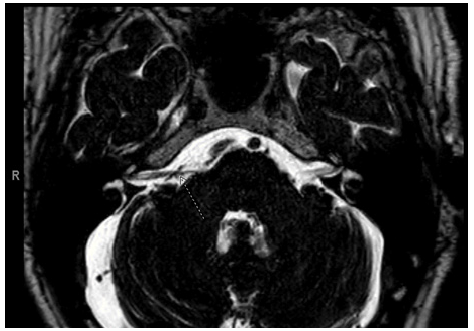

73-year-old white male with 15-year-history of intermittent stereotype episodes of non-spinning dizziness. He describes the episodes as a sudden sensation of shaking like if he was in an earthquake followed by a significant exacerbation of his underlying right tinnitus. These spells last for 15 and 20 seconds and occur with a frequency of 60-70 per day. These episodes have no triggers. He has history of migraine headaches, but none of his headache attacks are associated with these episodes of dizziness. He denied nausea and vomiting, weakness, paresthesia, and changes in mentation. Neuro-ophthalmological and neuro-otologic examination were unremarkable. Hallpike maneuver was negative. Vestibular laboratory testing revealed a right vestibular peripheral deficit with a caloric testing weakness [functional reduction of 65%] on the right and head-shaking-induced nystagmus towards the left. Audiogram showed a moderate to severe bilateral sensory neural deficit. A cardiac evaluation with a Holter during the dizziness attacks was unremarkable. Laboratory investigations including complete metabolic panel, inflammatory markers, syphilis, and cells counts were all unremarkable. Head MRI showed normal brain parenchyma and ventricular system. An axial T2-weighted sequences of the posterior fossa showed a vascular loop compressing the right eight cranial nerve. The MRA of his neck and head reveal no stenosis. Vestibular rehabilitation and therapy with meclizine had no effect, however he became asymptomatic with carbamazepine at the dosage of 200MG three times daily.

These findings support the diagnosis of Vestibular Paroxysmia [VP]. VP is a rare syndrome caused by neurovascular cross-compression of the vestibulocochlear nerve that present with intermittent spontaneous vertigo [1,2] (Figure 1).

Figure 1: T2-weighted axial images of the internal auditory canal showing a right aberrant anterior inferior cerebellar artery compressing the right vestibulocochlear nerve [arrow].